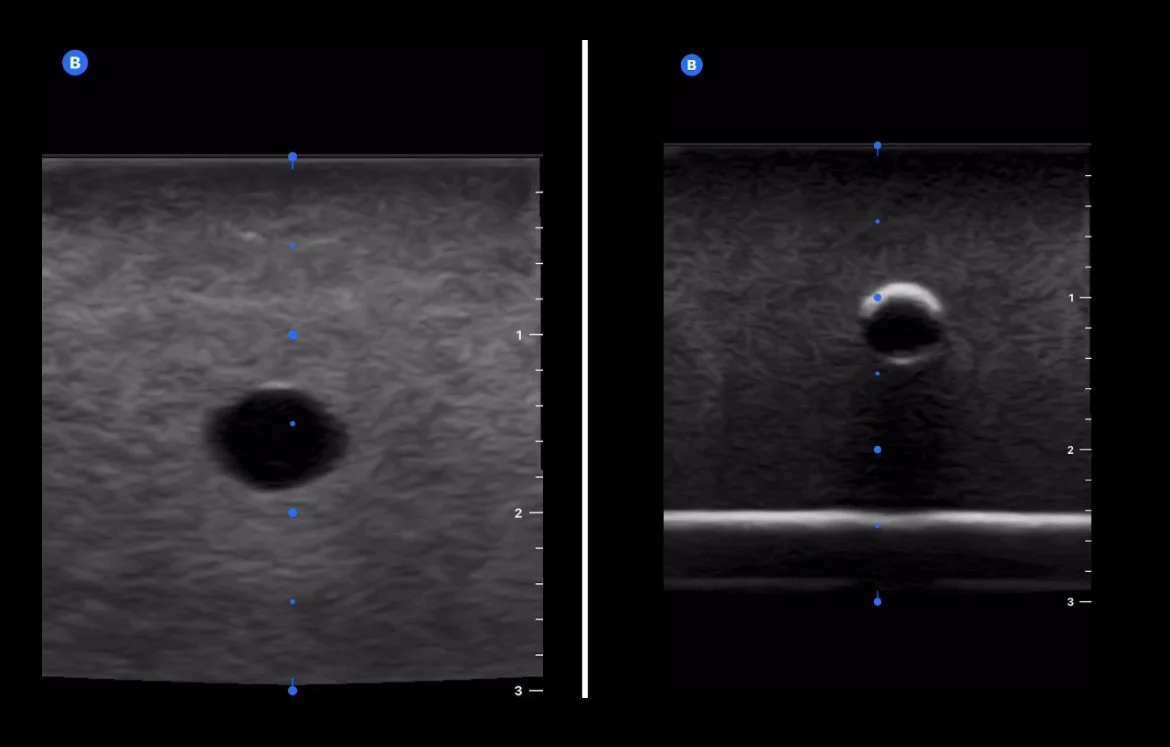

Prototype 2 (left) via Mindray versus Prototype 1 (right) via Butterfly.

Left is a $500 US phantom from a medical simulation company. Right is Prototype 2, which comes in at approximately $10.